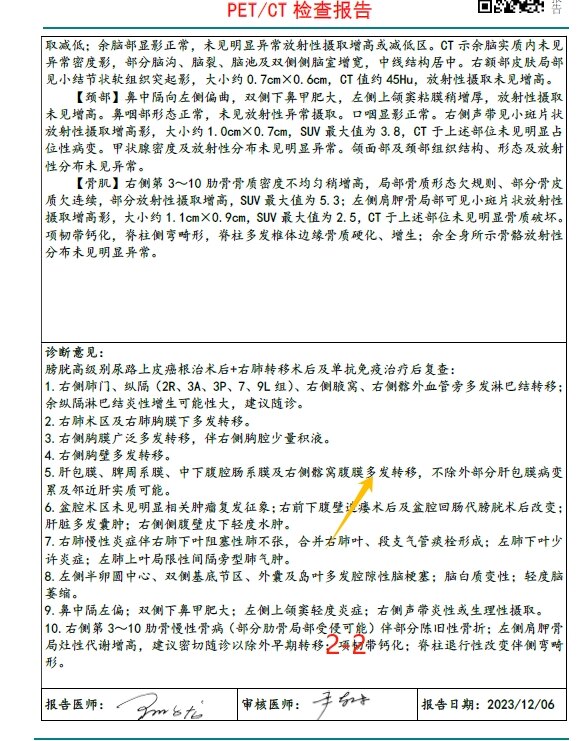

放疗前PET/CT(2023-12-06):

1

2